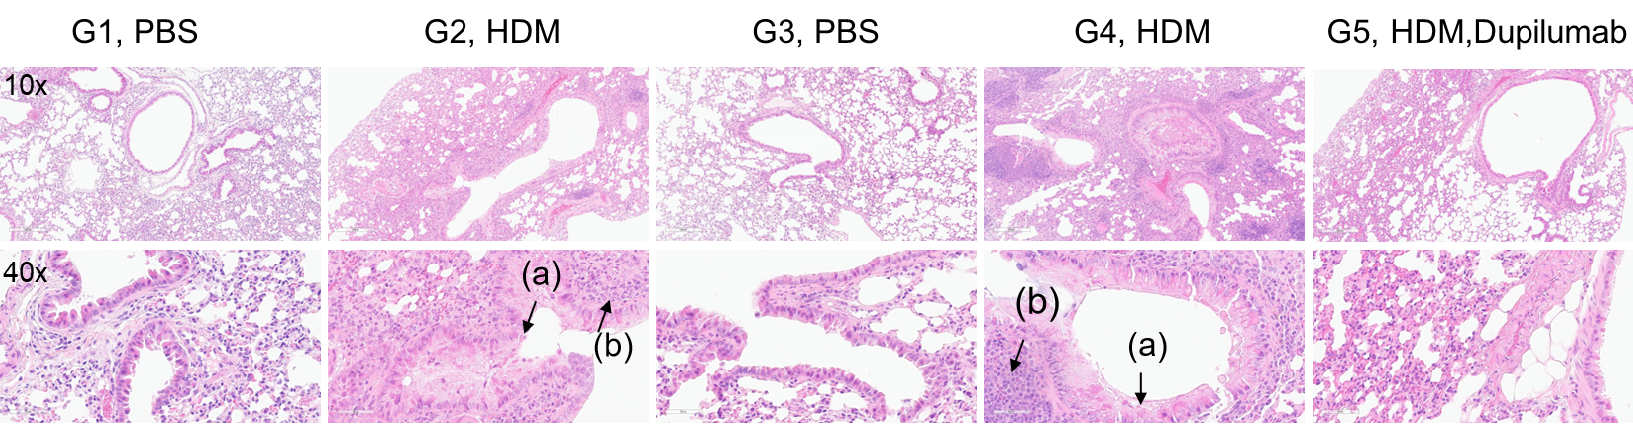

H&E staining of lung tissue in HDM-induced asthmatic mice. Compared to G1 (C57BL/6) and G3 (B-hIL4/hIL4RA) untreated controls, G2 (C57BL/6) and G4 (B-hIL4/hIL4RA) mice treated with house dust mite (HDM) exhibited hallmark asthma pathology, including peribronchial and perivascular mixed inflammatory cell infiltration (b) and mucus accumulation (a) in the bronchi. Dupilumab treatment significantly reduced these pathological features, demonstrating the therapeutic efficacy of anti-IL-4R blockade in an HDM-induced allergic asthma model.